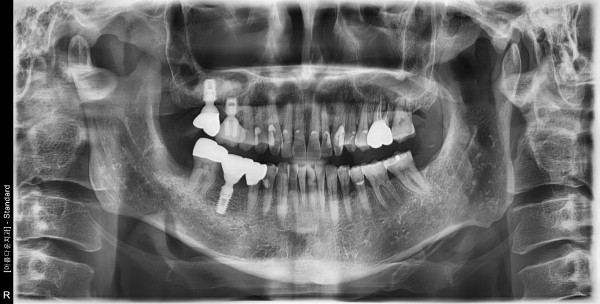

50대 남성 임플란트 식립